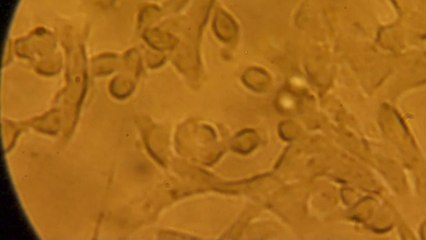

Manger moins, bouger plus est le mantra de la perte de poids depuis des siècles. Mais le poids n'est pas seulement la conséquence d'une mauvaise alimentation ou d'un manque de volonté. Même en tenant compte de la question des gênes, les scientifiques ont du mal à expliquer pourquoi certains peuvent se bourrer de gâteaux sans prendre un gramme tandis que les autres ne perdent pas un kilo en se contentant de haricots verts. Mais de récentes recherches ont révélé qu'il existait une pièce manquante très complexe au puzzle de l'obésité : l'action du microbiote.